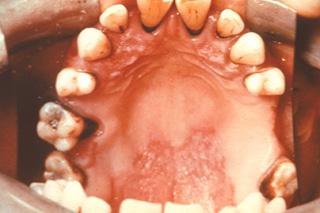

Lesiones orales, incluidas úlceras mucosas indoloras (Diagnostico diferencial con Behcet)

(Ver Figura 17)